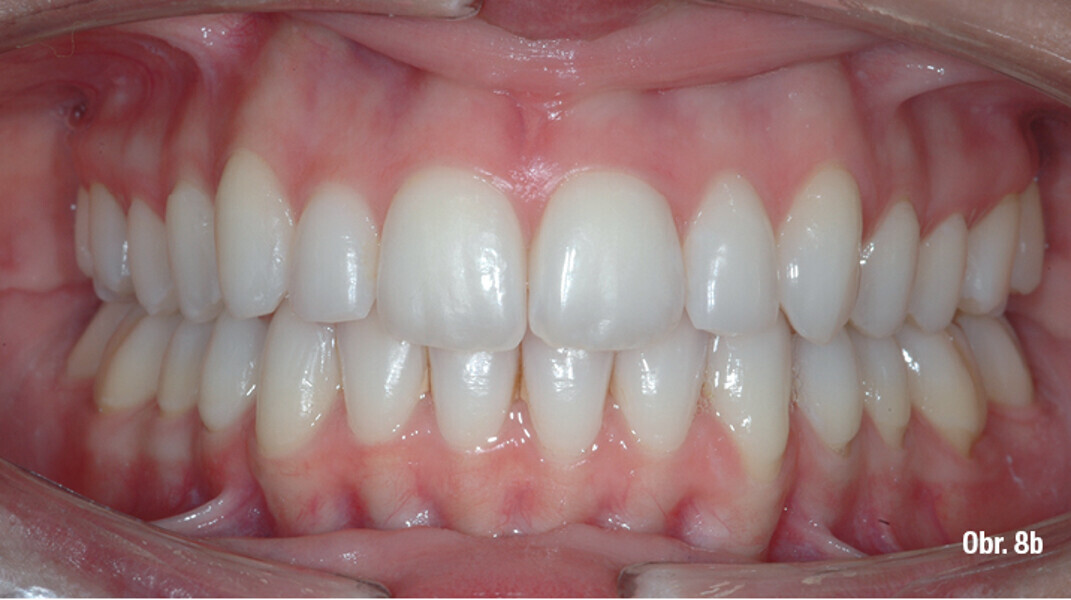

Distalizace horních molárů pomocí alignerů a cyklických sil